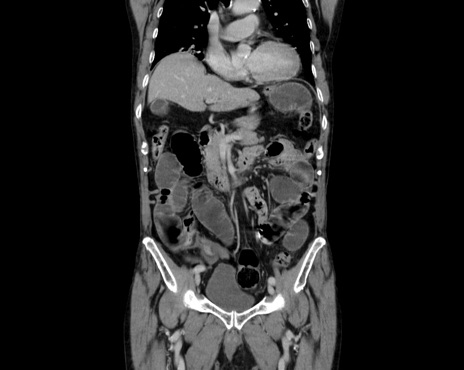

症例26(冠状断像)

【症例】80歳代男性

【主訴】嘔吐

【現病歴】昨晩2回嘔吐あり、今朝になっても嘔吐あり。来院。

【既往歴】胃潰瘍

【身体所見】意識清明、BT 37.6℃、BP 166/95mmHg、HR 100bpm、SpO2 97%、腹部:平坦・軟、腸蠕動音聴取良好、圧痛なし。

【データ】WBC 21900、CRP 1.4